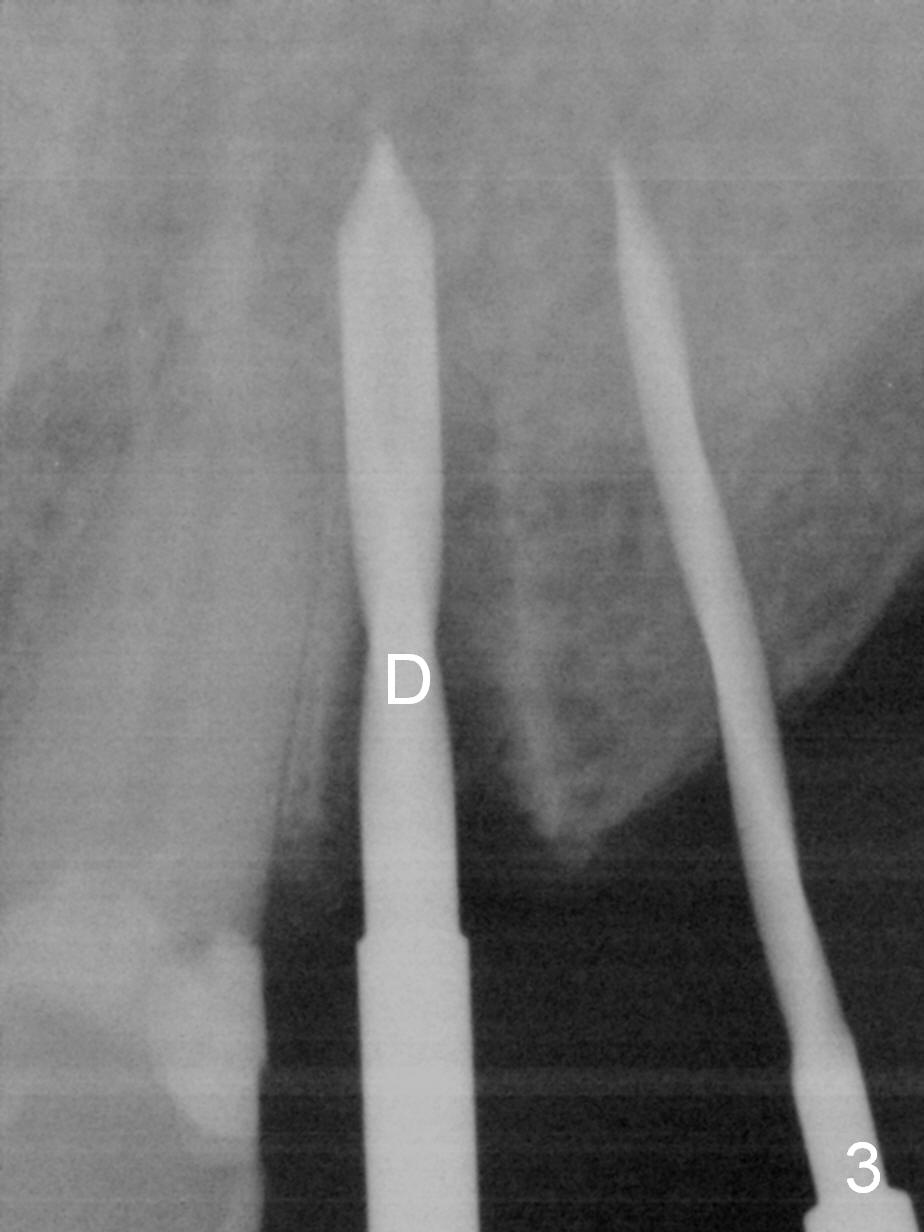

Six months post cementation of implant crown at #10, the tooth #9 becomes symptomatic with buccal apical swelling and tenderness (Fig.1). The implant and the neighboring root are close to each other. Due to extensive restoration and periapical radiolucency at #9 with percussion, root canal therapy begins with placement of calcium hydroxide. The pain reduces by the evening.